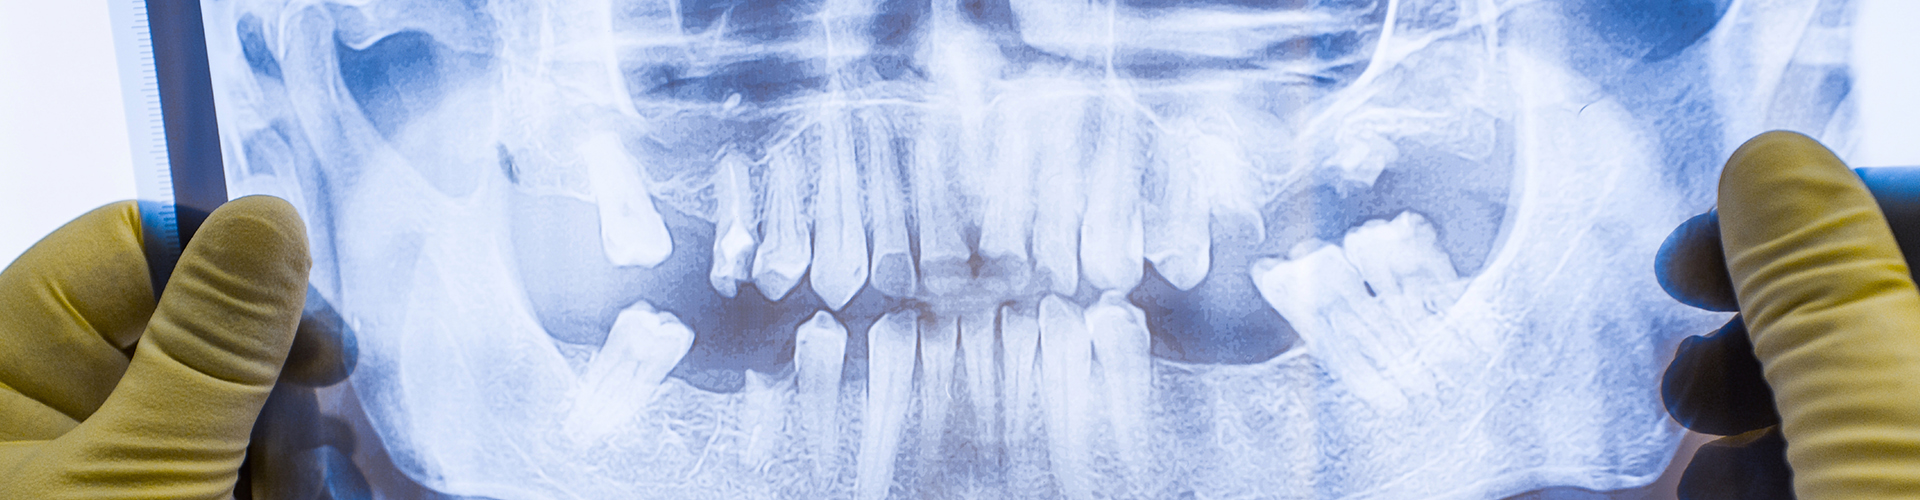

Panoramic Radiograph: also called an orthopantomogram is a two-dimensional (2-D) dental imaging tool that captures the entire mouth in a single image, including the teeth, upper and lower jaws, surrounding structures and tissues.

Panoramic Radiographs, use radiation to create flat images of teeth and mouth structures. These types of radiographs give a basic snapshot of the mouth, but they're limited to showing just one angle at a time.

Panoramic radiographs are primarily used to find cavities, and spot dental issues like fractures or probable infections in the mouth. While X-rays provide valuable diagnostic information, their ability to show complex structures or soft tissues is quite limited.

Panoramic radiographs are often used during regular dental check-ups, to find cavities, and evaluate the fit of dental restorations. They're also used in root canal treatments to see inside the roots for infections or problems.